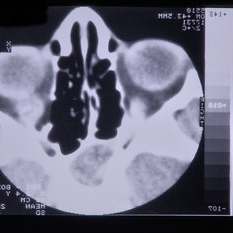

Rhabdomyosarcoma